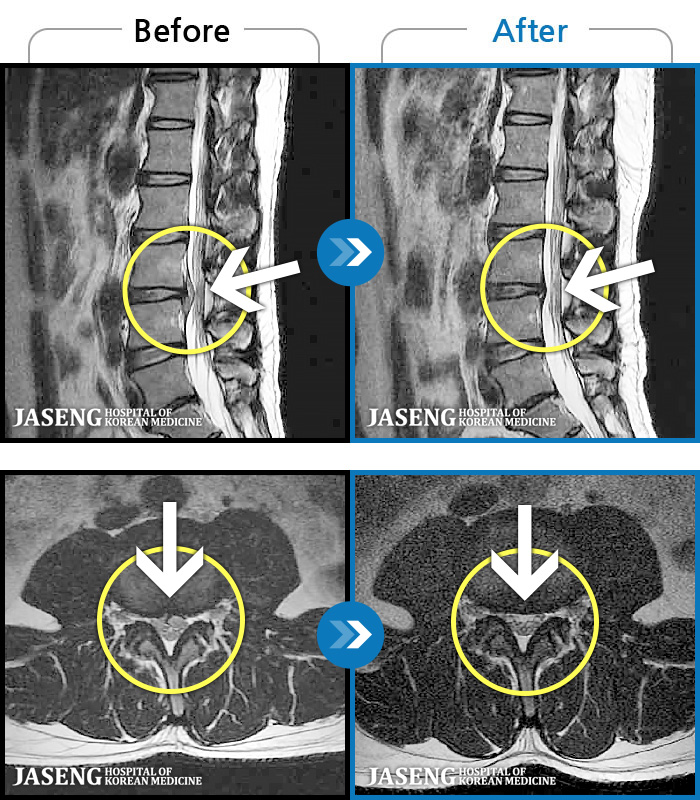

123 MRI ũ ʸ Ȯϼ.

ó ̾ ߰, ణ ٷϵ ݵǾ ϻȰ ¿ϴ. |

[õ] 24.04.06~24.11.16